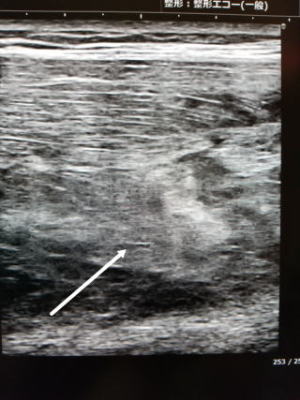

骨化性筋炎は、外傷や手術後などに局所で石灰化が起こり骨化する病気です。骨化が小さいものなら支障が無いこともありますが、大きくなると関節の可動域が障害され日常生活や運動で支障が出ることがあります。有名なのはコンタクトスポーツで相手の膝が太ももに入り、大腿四頭筋が損傷して血腫を形成し骨化するケースです。

自然経過が実際どうなるのか、はっきりと書いたものはありませんでした。今回の事例のように局所に負荷を掛けなければ、縮小してレントゲンで見えなくなり、また超音波でも著しく縮小することもあることが分かりました。おそらく、完全な骨化までには至らず、日常生活を普通に送る程度の局所安静の結果、生じた石灰化が吸収されたものと考えます。→海外の文献によると30%~40%ぐらいは吸収されて消失するとあります。

初診時(受傷2週間目)

蹴りを大腿に受けて受傷。正座をすると突っ張るとのことで来院。触診で大腿前面の腫れと皮下の硬結を認める。レントゲンでは骨傷なし。超音波では中間広筋内部に高エコーの石灰化を思わせる像を認めました。

*石灰化はレントゲンより超音波の方が遙かに感度が高いです。

受傷4週間目

レントゲンで大腿骨前面に石灰化を認めます。超音波では石灰化が成長してくっきりと見えています。

受傷7週間半

ご本人よりなんかすっきりしてきました。腫れも触れませんとのこと。レントゲンで石灰化は消失しています。また超音波でもかなり縮小してきています。触診で硬結は触れませんでした。